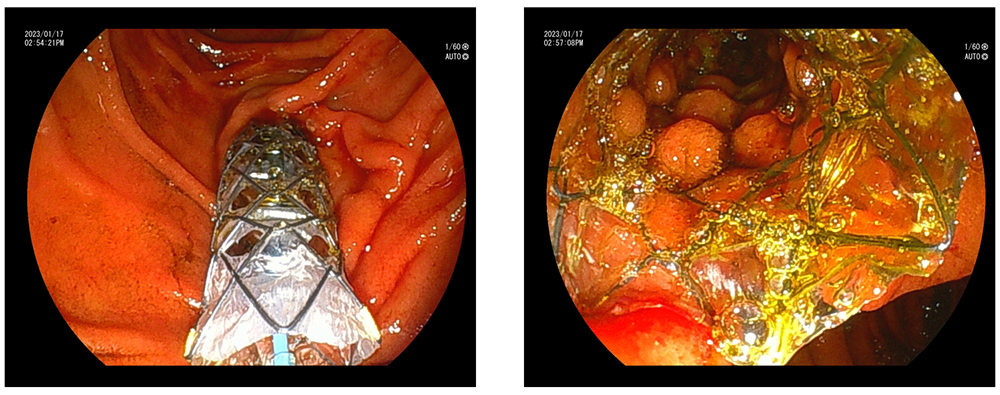

臨床画像

留置前後の臨床画像

| 画像提供: | 順天堂大学医学部附属順天堂医院 伊佐山 浩通 先生 順天堂大学医学部附属練馬病院 高橋 翔 先生 |